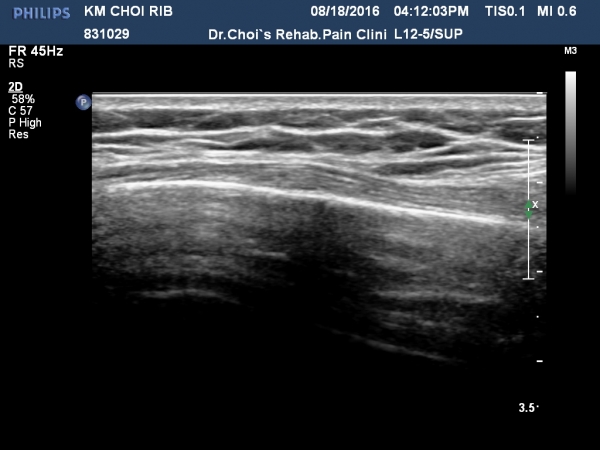

3ÁÖ ÈÄ ÃßÀû°Ë»ç¿¡¼­ °¡°ñ(callus)Çü¼ºÀÌ °üÂûµÈ´Ù(»çÁø 5, 6, 7, 8).